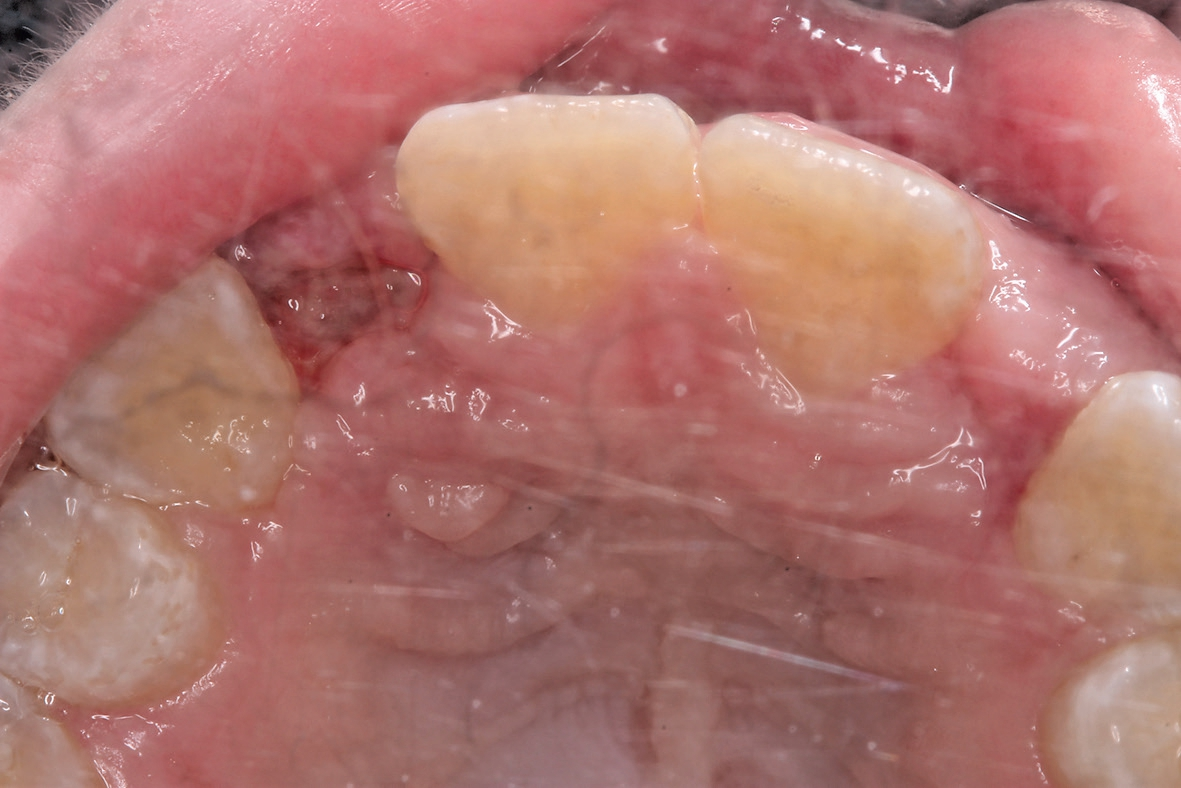

Eine 17-jährige Patientin wurde an unsere Praxis mit dem Wunsch nach einer festsitzenden implantatprothetischen Versorgung der lateralen Schneidezähne 12 und 22 überwiesen. Nach entsprechender Aufklärung und intensiver Beratung wurde zunächst ein DVT erstellt, um das genaue Ausmaß der dreidimensionalen Knochenresorption in regio der fehlenden lateralen Schneidezähne regio 12 und 22 beurteilen zu können. Die röntgenlogische Auswertung ergab eine hochgradige horizontale Alveolarfortsatzbreite von knapp 3 mm in regio 12 respektive von knapp 2,5 mm in regio 22 mit stark ausgeprägter konkaver Kontur der bukkalen Lamelle (Abb. 1). Allein das klinische Bild (Abb. 2 und 3) zeigte eine ausgeprägte horizontale Alveolarfortsatzatrophie in regio 12 und 22 mit ausgeprägten Konkavitäten in der bukkalen Lamelle.

Letztendlich bestand aus kieferorthopädischer Sicht keine Kontraindikation für eine unverzügliche chirurgische Intervention mit nachfolgender implantatprothetischer Versorgung bei derart fortgeschrittener horizontaler Atrophie in regio 12 und 22 (2,5 mm mit großer Konkavität). Insofern wurde nach erneuter intensiver dokumentierter Beratung und Aufklärung wie auch wirtschaftlicher Aufklärung nach entsprechender beidseitiger Leitungsanästhesie am Foramen infraorbitale und zusätzliche intraoralen und vestibulären Infiltrationsanästhesien zunächst ein breiter Mukoperiostlappen von regio 14 bis 24 gebildet (Abb. 4) und zur Förderung der Durchblutung des allogenen Transplantates wurden entsprechende Bleeding-Points (entsprechende Perforation der bukkalen Kortikalis) gesetzt (Abb. 5). Die mit Hilfe von CAD/CAM durch das Labor ProDent (Zahntechnikermeister Thomas Blaschke) hergestellten kortikospongiösen Blöcke nach DVT-Auswertung wurden mit entsprechenden Osteosyntheseschrauben fixiert (Abb. 6) und mögliche Restspalträume mit allogener Spongiosa abgedichtet und lateral auskonturiert.